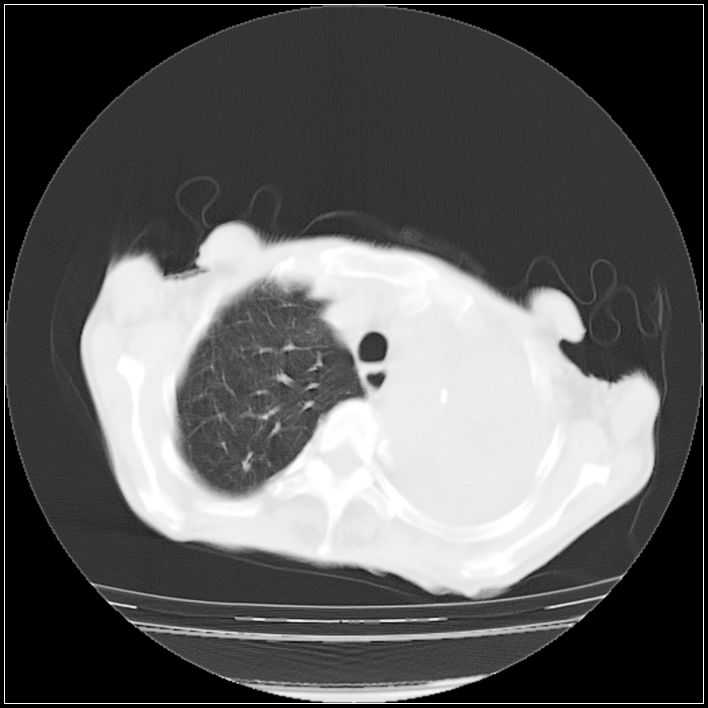

以下是引用ydx_74在2008-5-31 16:08:00的发言:[br]中心性肺癌并左侧肺不张、胸水。

以下是引用影象小辈在2008-5-31 16:25:00的发言:[br]左侧胸腔团状不规则致密影,界欠规整,密度不均匀,其内可见更低密度影及高密度影,并可见包裹性胸腔积液 考虑为1.畸胎瘤 2.肺癌